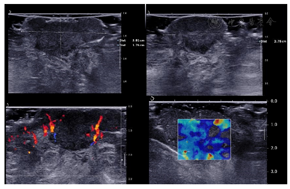

皮肤肿物及引流区淋巴结超声提示:右侧会阴部及肛门偏左侧皮下软组织内分别见混合回声区,大小25 mm×11 mm,13 mm×9 mm,形态不规则,边界不清晰,内部回声不均匀。周边皮下软组织肿胀,回声增高。病灶内部及周边可见血流信号。剪切波弹性成像提示病灶较周围组织硬(图2、图3)。双侧腹股沟区可见数个低回声区,较大者大小28 mm×17 mm,形态不规则,边界尚清晰,内部回声不均匀,皮髓质分界不清,未见淋巴门样结构。内部见血流信号(图4)。右侧会阴部及肛门偏左侧皮下软组织内实性结构,恶性病变可能性大。双侧腹股沟区实性结构,考虑异常淋巴结。